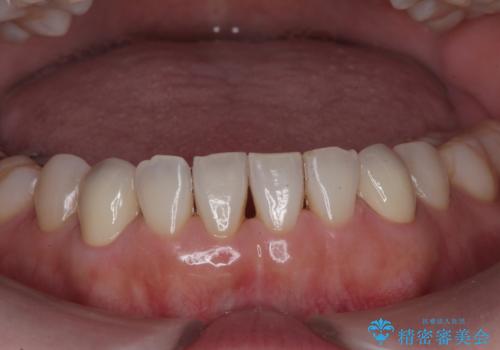

最近右下の犬歯の根の先付近の歯茎に何かできており、違和感があるとのでした。

CTでみたところ、下の犬歯が内側に倒れこんでおり、根の先が顎の骨から出かかっている状態でした。おそらくその影響で犬歯の神経が失活してしまったのであろうと思われます。(フェネストレーションといいます)

検査した結果下の両側の犬歯の神経が失活しており、根の治療が必要な状態でした。